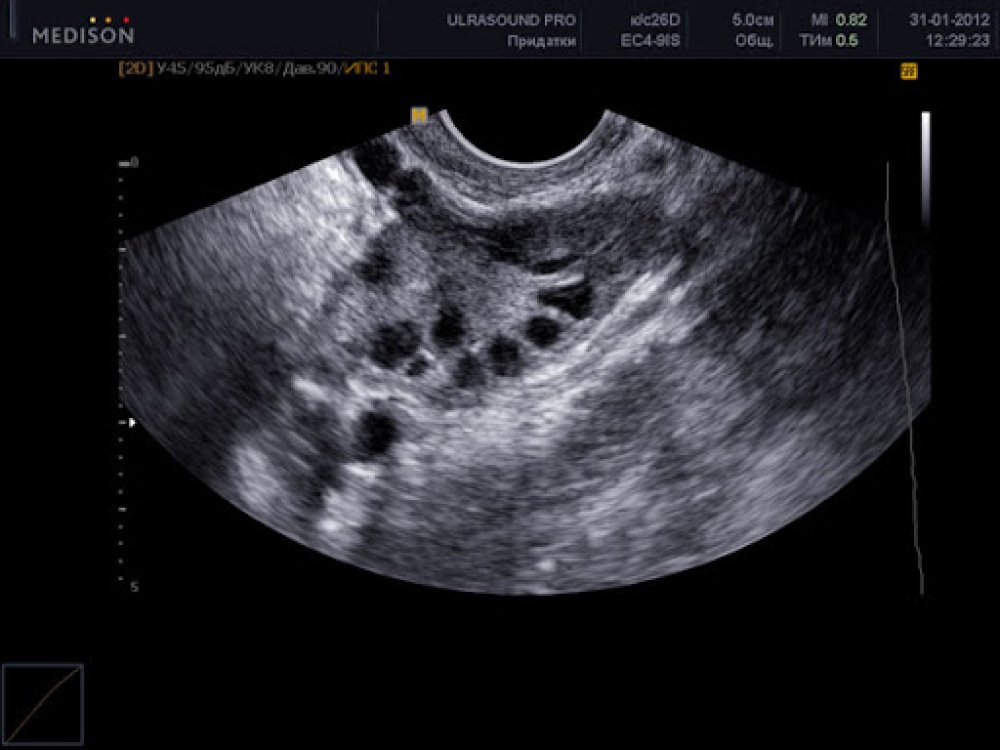

Yumurtalığın transplantasiyası

İlk yumurtalıq transplantasiyasından artıq 14 il keçir. 2007-ci ildə doktor Şerman  Silber Suzan Butçerə yumurtalıq köçürmüşdü. Suzan  üçün donor onunla eyni yaşda -38 yaşında olan bacısı idi. Həmin əməliyyat təxminən 4,5 saat çəkdi.  Sonsuzluqdan əziyyət çəkən qadın transplantasiyadan bir il sonra  hamilə qaldı.